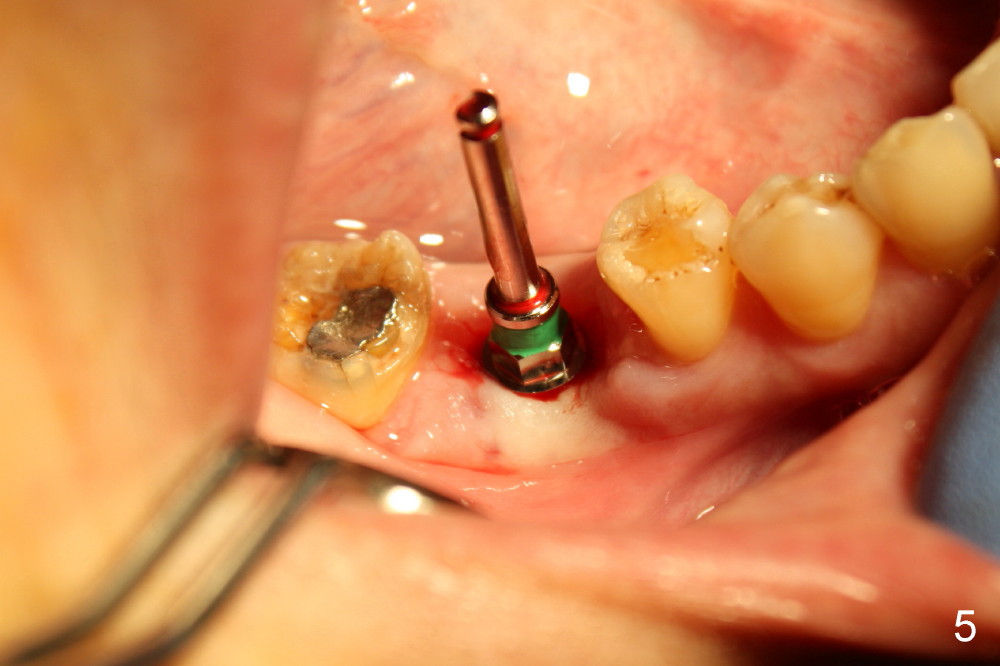

The socket of #30 heals one month after extraction (Fig.1 *). What is unexpected is that the alveolus has started to shrink (follows arrowheads). It is also unexpectedly easy to tap in RT2 (flapless). With insertion of a 2.0 mm pilot drill, PA reveals that osteotomy is not inside the septum (Fig.2 S). Redirecting osteotomy with the same pilot drill leads to insertion into the septum, but the upper end of the pilot drill should be moved mesially in next steps (arrow). With that and treatment plan in mind, combination of osteotomes, Bicon reamers and taps results in right trajectory (Fig.4 * (5x20 tapered tap), Fig.5 (6x17 tapered tap)). Harvested bone (Fig.6) is transferred to the mesial socket and condensed (Fig.7). Insertion torque of 6x17 mm implant is more than 60 Ncm. The lower end of the implant remains in the center of the septum (Fig.8 <). The gingiva contacts the implant tightly (Fig.9, 10) except mesiobucally (Fig.9 <). Periodontal dressing is used to protect the wound (Fig.11,12).